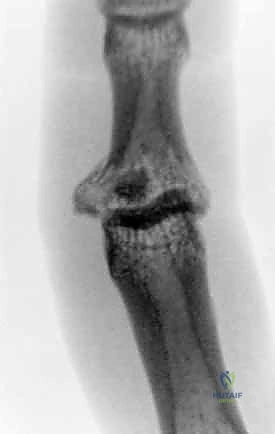

- الخلع الظهري مع كسر (Dorsal Fracture-Dislocation): وهو النوع الأكثر شيوعًا. يحدث عندما تندفع السلامية الوسطى للخلف (نحو ظهر اليد). يترافق عادة مع تمزق الصفيحة الراحية وكسر في الجزء الراحي (السفلي) من قاعدة السلامية الوسطى.

2. التصوير بالأشعة السينية (X-Rays)

هو المعيار الذهبي الأولي. يجب أخذ صور شعاعية واضحة ومحددة للإصبع المصاب (وليس لليد بأكملها) في ثلاث وضعيات:

* الوضعية الأمامية الخلفية (AP): لتقييم المحور الجانبي للإصبع والبحث عن شقوق عظمية.

* الوضعية الجانبية الحقيقية (True Lateral): هي الصورة الأهم على الإطلاق. من خلالها يتم تحديد حجم القطعة العظمية المكسورة، ومقدار انزياح المفصل. يبحث الجراح الماهر هنا عن علامة "V-Sign" الشهيرة، والتي تدل على عدم تطابق الأسطح المفصلية ووجود خلع جزئي غير مستقر.

* الوضعية المائلة (Oblique): تساعد في رؤية تفاصيل الكسور المفتتة التي قد تختفي في الوضعيات الأخرى.